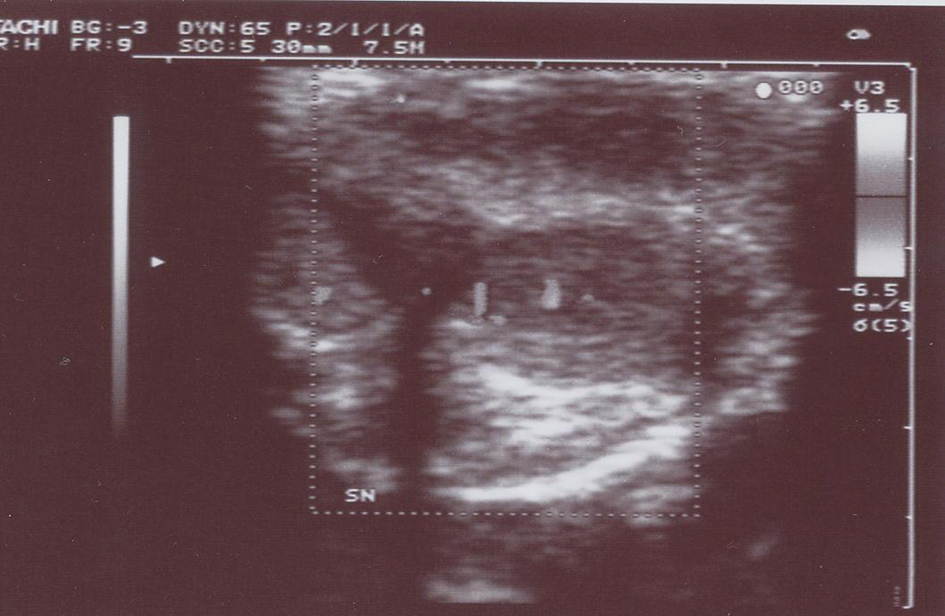

Over the last 12 months two men (71 years old and 72 years old, respectively) presented with a hard and elastic egg-shaped node of the penis. One of the patients had a history of several recurrences of NHL. We performed an ultrasonography (Fig. 1) with needle biopsy of the lesion in both patients [1] and the pathological examination showed in one case a NHL small cell type and in the other case a NHL mantellar cell type. An abdominal CT scan did not show any evidence of nodal involvement. The two patients were also assessed by the 15 questions-IIEF questionnaire which gave a score of 16 and 18, respectively. So a polichemotherapic treatment by ciclophosphamide, vincristine and prednisone has been decided. We repeated the therapy three times in 40 days. After that we reassessed the two patients by a physical examination and an ultrasonography of the penis. At that moment there was a complete resolution of penile NHL localisation in both patients, though in one of them a leucopenia and splenomegalia occurred and dissuaded from repeating other chemotherapic cycles.

![]() Click for large image | Figure 1. Ultrasonography of the lesion. |